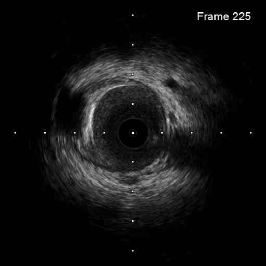

IVUS provides 2D grayscale images of vessel wall structures in 360 degrees, offering real-time imaging during surgery at video-rate speed without the need for contrast, as compared to Optical Coherence Tomography (OCT) (Li et al. 2022; Hui et al. 2017). Despite its advantages, IVUS generates low-resolution grayscale images with indistinct borders, as illustrated in Figure 1. This low resolution, common in ultrasonography, makes diagnosis more challenging. Plaque regions on IVUS images are typically identified manually by doctors using their naked eyes, relying heavily on extensive experience and professional knowledge. However, this traditional approach carries the risk of misjudgment due to the inherent subjectivity and complexity of the process.

• In diagnosis, the proposed method is intended to overcome the difficulty of detecting circular boundaries (Figure 1) for improving the treatment efficiency by area segmentation models. Data are preprocessed with coordinate conversions, and lumen and EEM areas are segmented with parallel U-Net models. The plaques are identified by subtracting both locations from one another.

(a) Original 2D IVUS image

Figure 1: Fragmentary boundaries after edge detection on IVUS images